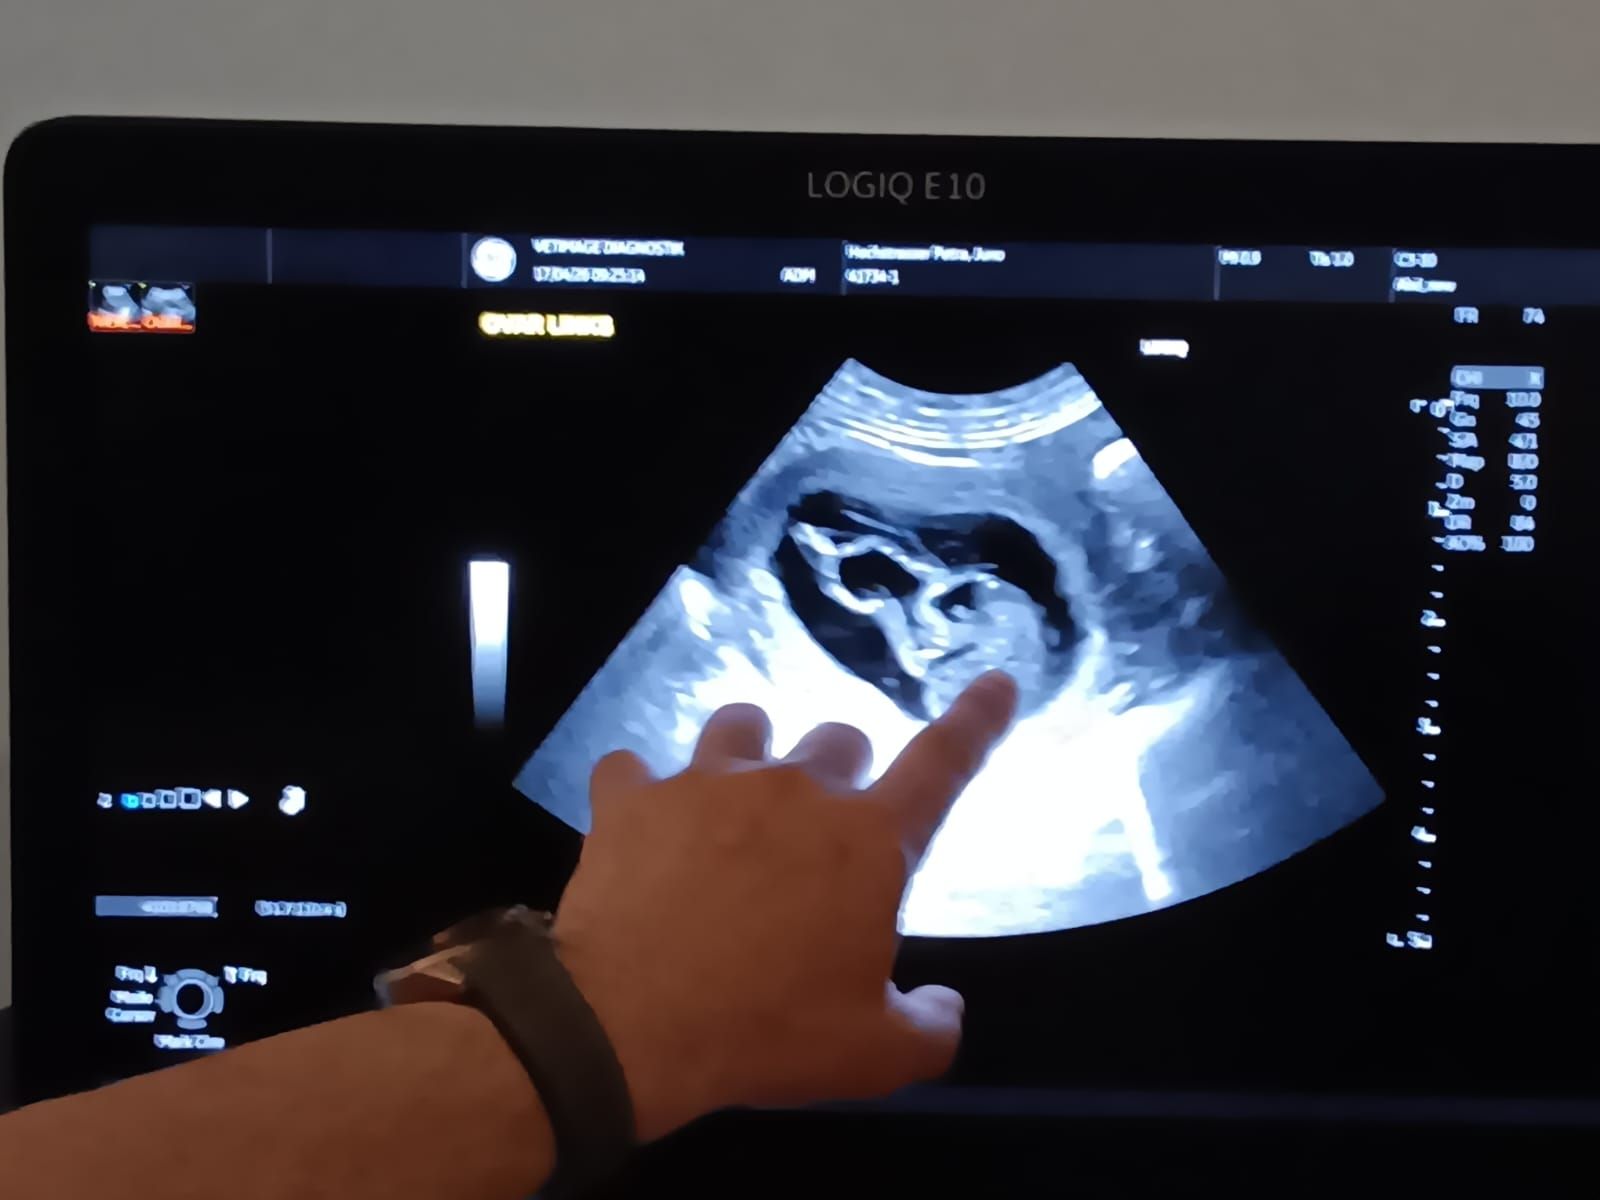

Hier sieht man ein Ultraschallbild eines Föten am 30. Tag nach dem Decken.